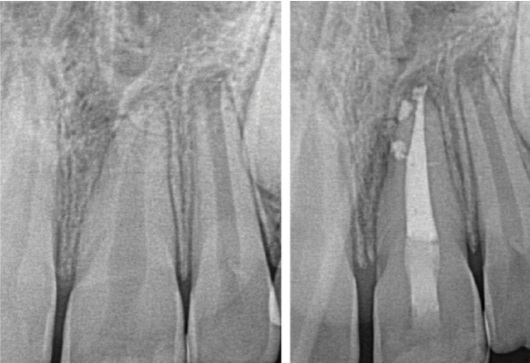

The EdgeOne Blaze Utopia file system is available in four tip sizes (ISO 20 to 45). File selection is based on canal anatomy. R35 or R45 are suitable for large, straight canals such as maxillary anterior teeth and mandibular premolars (Fig. 2). R25 is appropriate for most low- to moderate-difficulty cases, such as maxillary premolars and molars with patent, non-severely curved canals (Fig. 3). R20 is recommended for small, narrow canals and canals with more severe curvature to better follow the original anatomy and minimize procedural errors.

Fig. 3: Pre- and post-operative radiographs and clinical photos of tooth #30 as an example of a case with moderate difficulty prepared with EdgeOne Blaze Utopia R25.